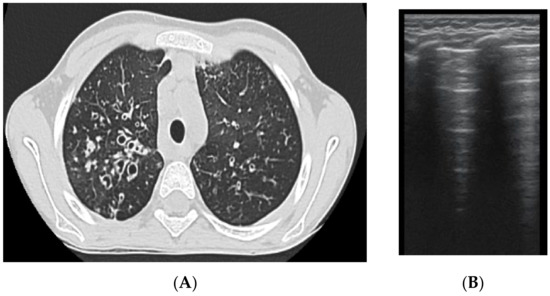

The assessment of LUS sensitivity and specificity in bronchiectasis detection varied with the form of bronchiectasis: for cylindrical bronchiectasis(Figure 8A,B), LUS Se = 77.7%, Sp = 9%, PPV = 80.7%, and NPV = 76.9%, while for saccular bronchiectasis (Figure 7), a moderate Se = 68.4%, with good Sp = 94.9%, PPV = 88.8%, and NPV = 94.7% were found.

As for varicose bronchiectasis (Figure 9 A,B), a very low Sp = 25% and NPV = 16.6% were calculated, with a satisfactory PPV = 88.8% and Se = 68.4%.

The results regarding atelectasis (Figure 10 and Figure 11) and consolidation detection were significant. LUS showed good sensitivity and specificity in detecting atelectasis (Figure 10)—Se = 83.7%, Sp = 94.5%, PPV = 92.5%, NPV = 72.3%—and consolidations—Se = 94.4%, Sp = 93.02%, PPV = 89.4%, NPV = 97.3%.

Figure 8. (A) CT scan: cylindrical bronchiectasis with mucus plugs (B) LUS: A lines, normal LUS aspect, score = 0.

Figure 9. (A) LUS: coalescent B lines, loss of A lines. (B) CT image: (1) cylindrical bronchiectasis with moderate wall thickening; (2) varicose bronchiectasis; (3) saccular bronchiectasis with moderate wall thickening; and (4) several bronchiectasis with mucus plugging.

Figure 10. (A) LUS image of atelectasis, hypoechoic image with air inside. (B) CT scan reveals atelectasis, bronchiectasis, and partial bronchogram.

Figure 11. (A) LUS image of atelectasis, consolidation without bronchogram. (B) CT exam illustrates (1) a peribronchovascular consolidation without air bronchogram, and (2) a lamellar (band) atelectasis.